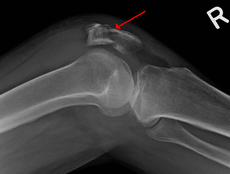

A fracture of the patella seen on a lateral view

A patella fracture is a fracture of the kneecap, which is one of the most common knee injuries. It is usually the result of a hard blow to the front of the knee. Treatment options for patella fracture include nonsurgical and surgical options, depending on the type of fracture.